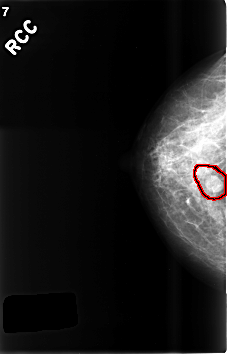

C_0507_1.RIGHT_CC

FILE: C_0507_1.RIGHT_CC.OVERLAY

TOTAL_ABNORMALITIES 1

ABNORMALITY 1

LESION_TYPE MASS SHAPE OVAL MARGINS CIRCUMSCRIBED

ASSESSMENT 3

SUBTLETY 5

PATHOLOGY BENIGN

TOTAL_OUTLINES 2

BOUNDARY